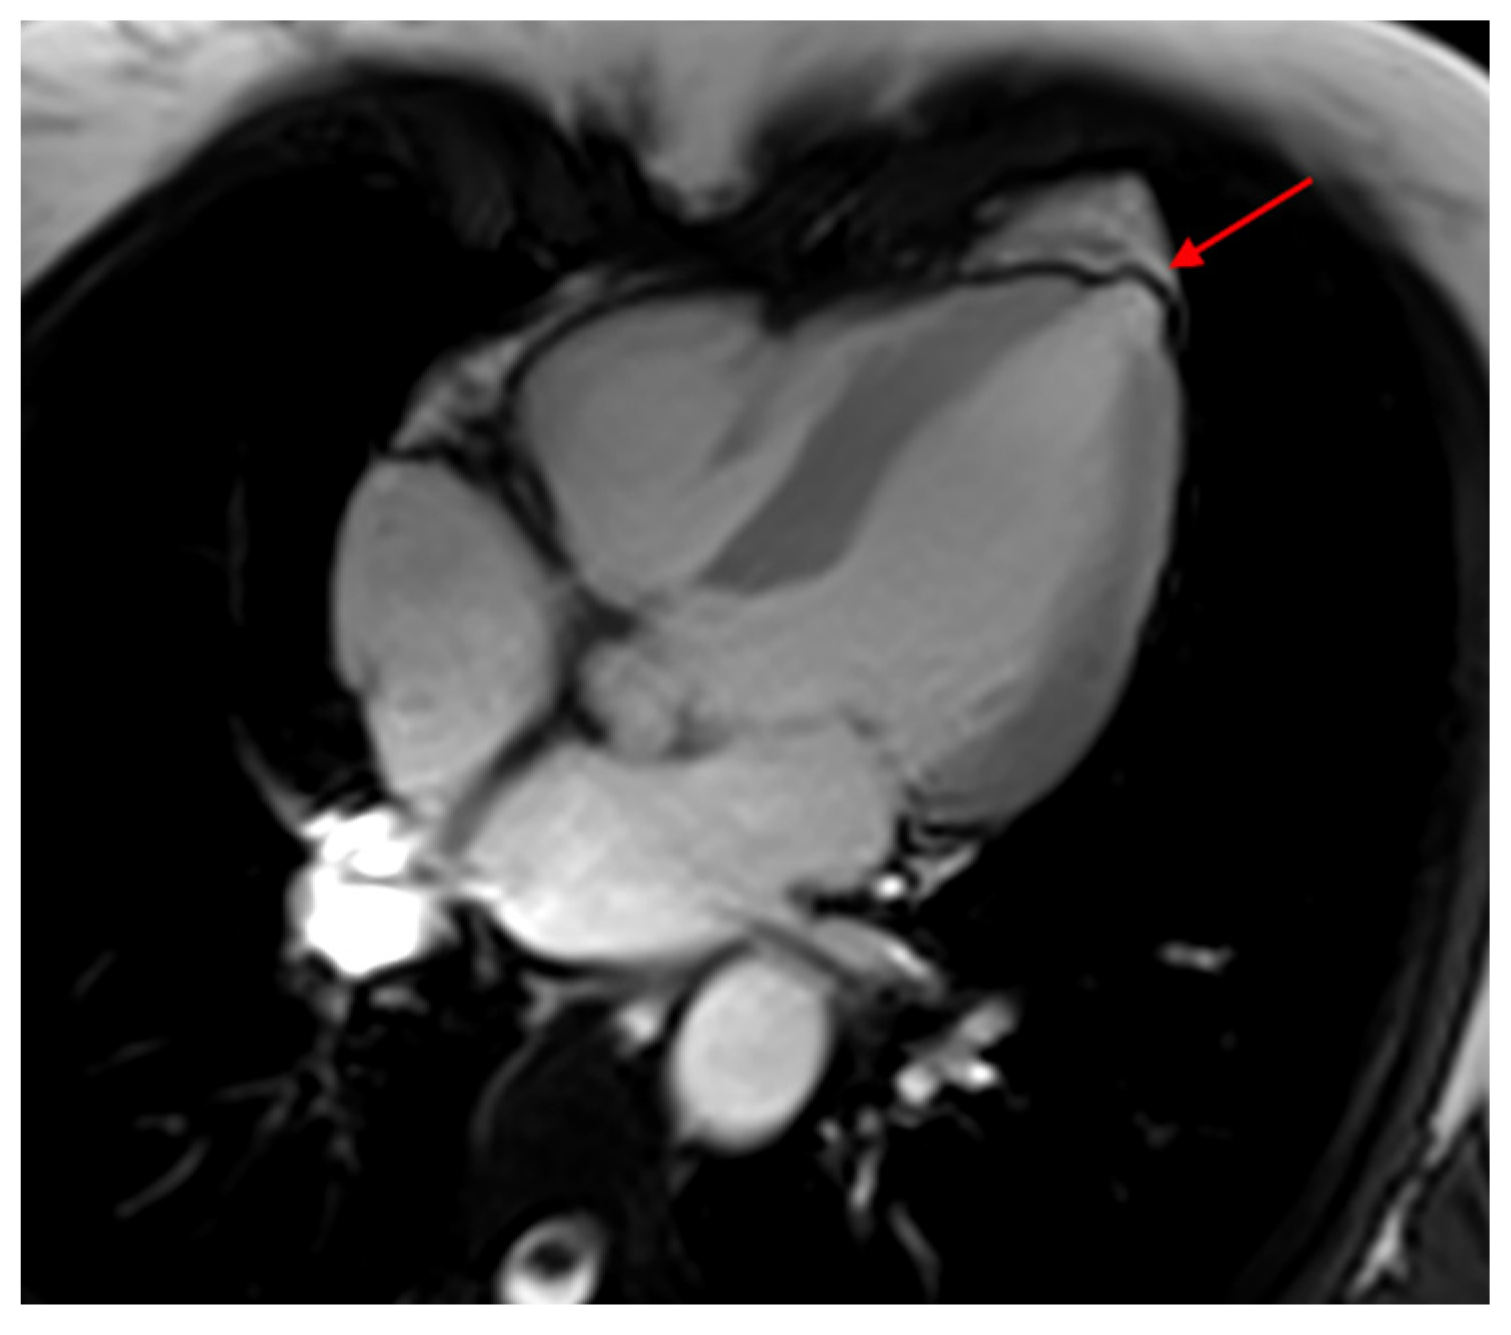

- Moll-Bernardes, R.J.; Saraiva, R.M.; Sarmento de Oliveira, R.; Tavares Pinheiro, M.V.; Camargo, G.C.; Xavier de Brito, A.S.; Altino de Almeida, S.; Siqueira, F.P.; de Souza Nogueira Sardinha Mendes, F.; Barbosa, R.M. Case Report: Malignant Ventricular Arrhythmias Mimicking Acute Coronary Syndrome in Chagas Disease. Am. J. Trop. Med. Hyg. 2020, 102, 797–799. [Google Scholar] [CrossRef]

- Shapiro, H.; Meymandi, S.; Shivkumar, K.; Bradfield, J.S. Cardiac inflammation and ventricular tachycardia in Chagas disease. HeartRhythm Case Rep. 2017, 3, 392–395. [Google Scholar] [CrossRef] [PubMed]

- Moll-Bernardes, R.J.; de Oliveira, R.S.; de Brito, A.S.X.; de Almeida, S.A.; Rosado-de-Castro, P.H.; de Sousa, A.S. Can PET/CT be useful in predicting ventricular arrhythmias in Chagas Disease? J. Nucl. Cardiol. 2020, 1–4. [Google Scholar] [CrossRef] [PubMed]